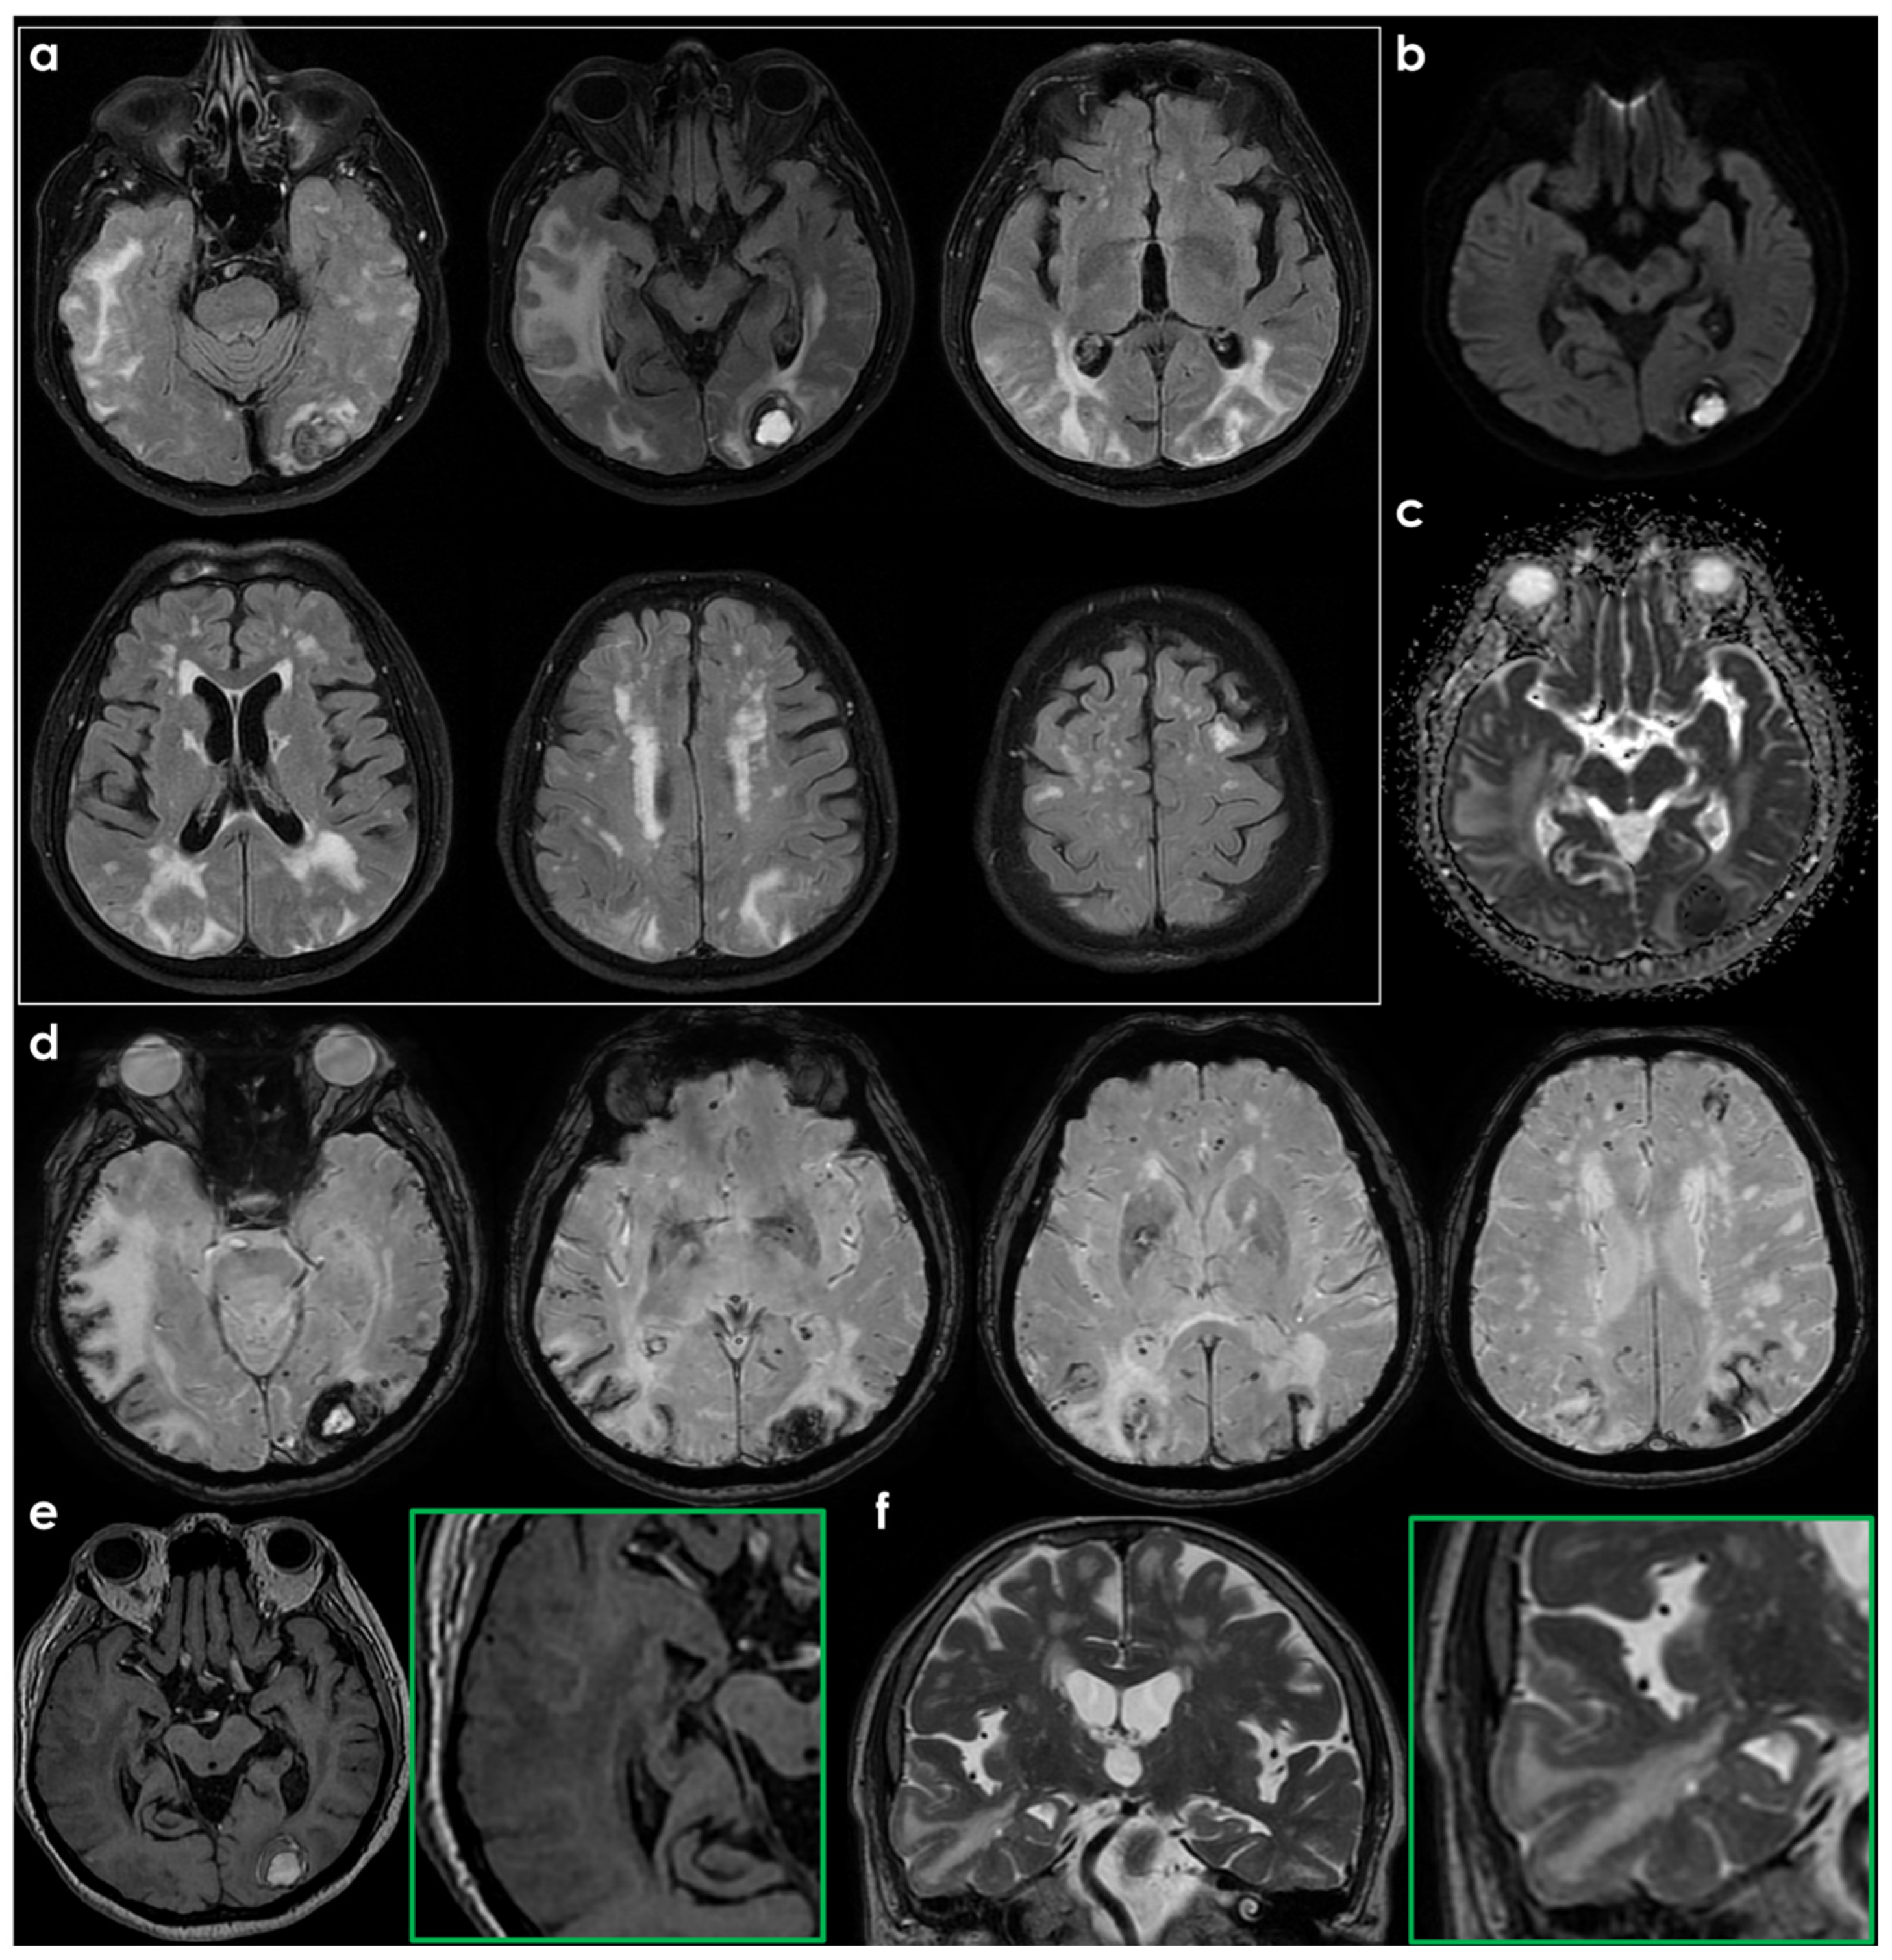

- ARIA-E (Edema/Effusion), characterized by focal regions of white matter hyperintensities (WMH), or increased signal intensities within the cortical sulci, reflecting the accumulation of protein-rich fluid within the leptomeningeal and sulcal spaces, consistent with an exudative inflammatory process.

- ARIA-H (Hemorrhage), defined by the appearance of CMB, cSS, or Intracerebral Hemorrhage (ICH). These findings are thought to arise from lesions related to CAA, as a result of the weakening of vessel walls and their subsequent rupture.

| Neuroimaging characteristics | CAA-ri is usually characterized by: -Unifocal or multifocal hyperintense lesions (cortico-subcortical or deep) that are asymmetric and extend to the immediately subcortical white matter -Presence CMB or cSS, frequently colocalized with ARIA-E Although not included in the CAA-ri diagnostic criteria, leptomeningeal involvement similar to the drug-induced counterpart have been described. | ARIA-E may present as parenchymal edema, sulcal effusion, or a combination of both. The imaging pattern is similar to vasogenic edema, represented by hyperintense signal on T2-FLAIR in the white matter, gray matter, or both. There may be associated local mass effect and gyral swelling. ARIA-H includes CMB, cSS (frequently colocalized with ARIA-E), or lobar ICH. |